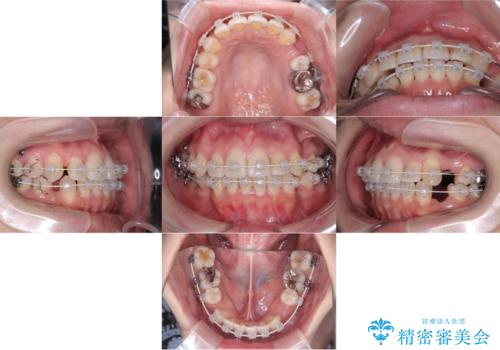

【ワイヤー矯正】口元を下げたい、下の歯の凹凸を無くしたい

- 主訴:口元を下げて前突感を無くしたい、下の歯の凹凸も無くしたい

右側第二小臼歯、左側第一小臼歯、下顎両側第一大臼歯を抜歯しワイヤ-矯正を行いました。

骨格的顎の変位を認めたため、顔貌に対しピッタリ上下の歯の正中を合わせることは難しいと説明し、上下左右計4本小臼歯を抜歯しワイヤー矯正治療を行いました。